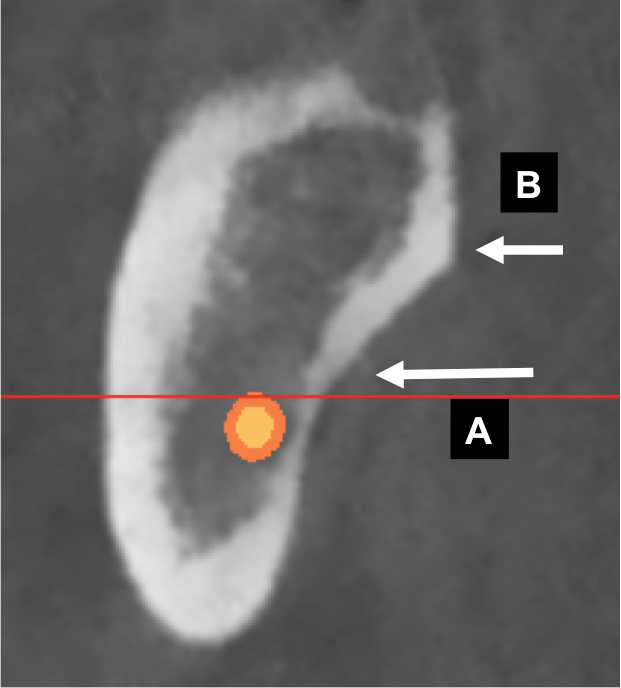

Fig 1. Mandibular foramen and lingula: cross-sectional view. A: The mandibular nerve enters the ramus at the mandibular foramen. B: The lingula is a ridge of bone superior to the mandibular foramen and provides attachment for the sphenomandibular ligament.

One of the first landmarks noticed in the posterior mandible is the mandibular foramen. At this site, the inferior alveolar nerve enters the ramus (Figure 1). When administering a mandibular block injection, it is often advisable to insert the needle 6 mm to 10 mm above the occlusal plane,5 because the mandibular canal is coronal to the occlusal plane 2% to 25% of the time.6,7 Therefore, an injection at the occlusal plane may result in failure to attain a good anesthetic result. The ridge superior to the foramen is the lingula, and the sphenomandibular ligament inserts at this location (Figure 1).